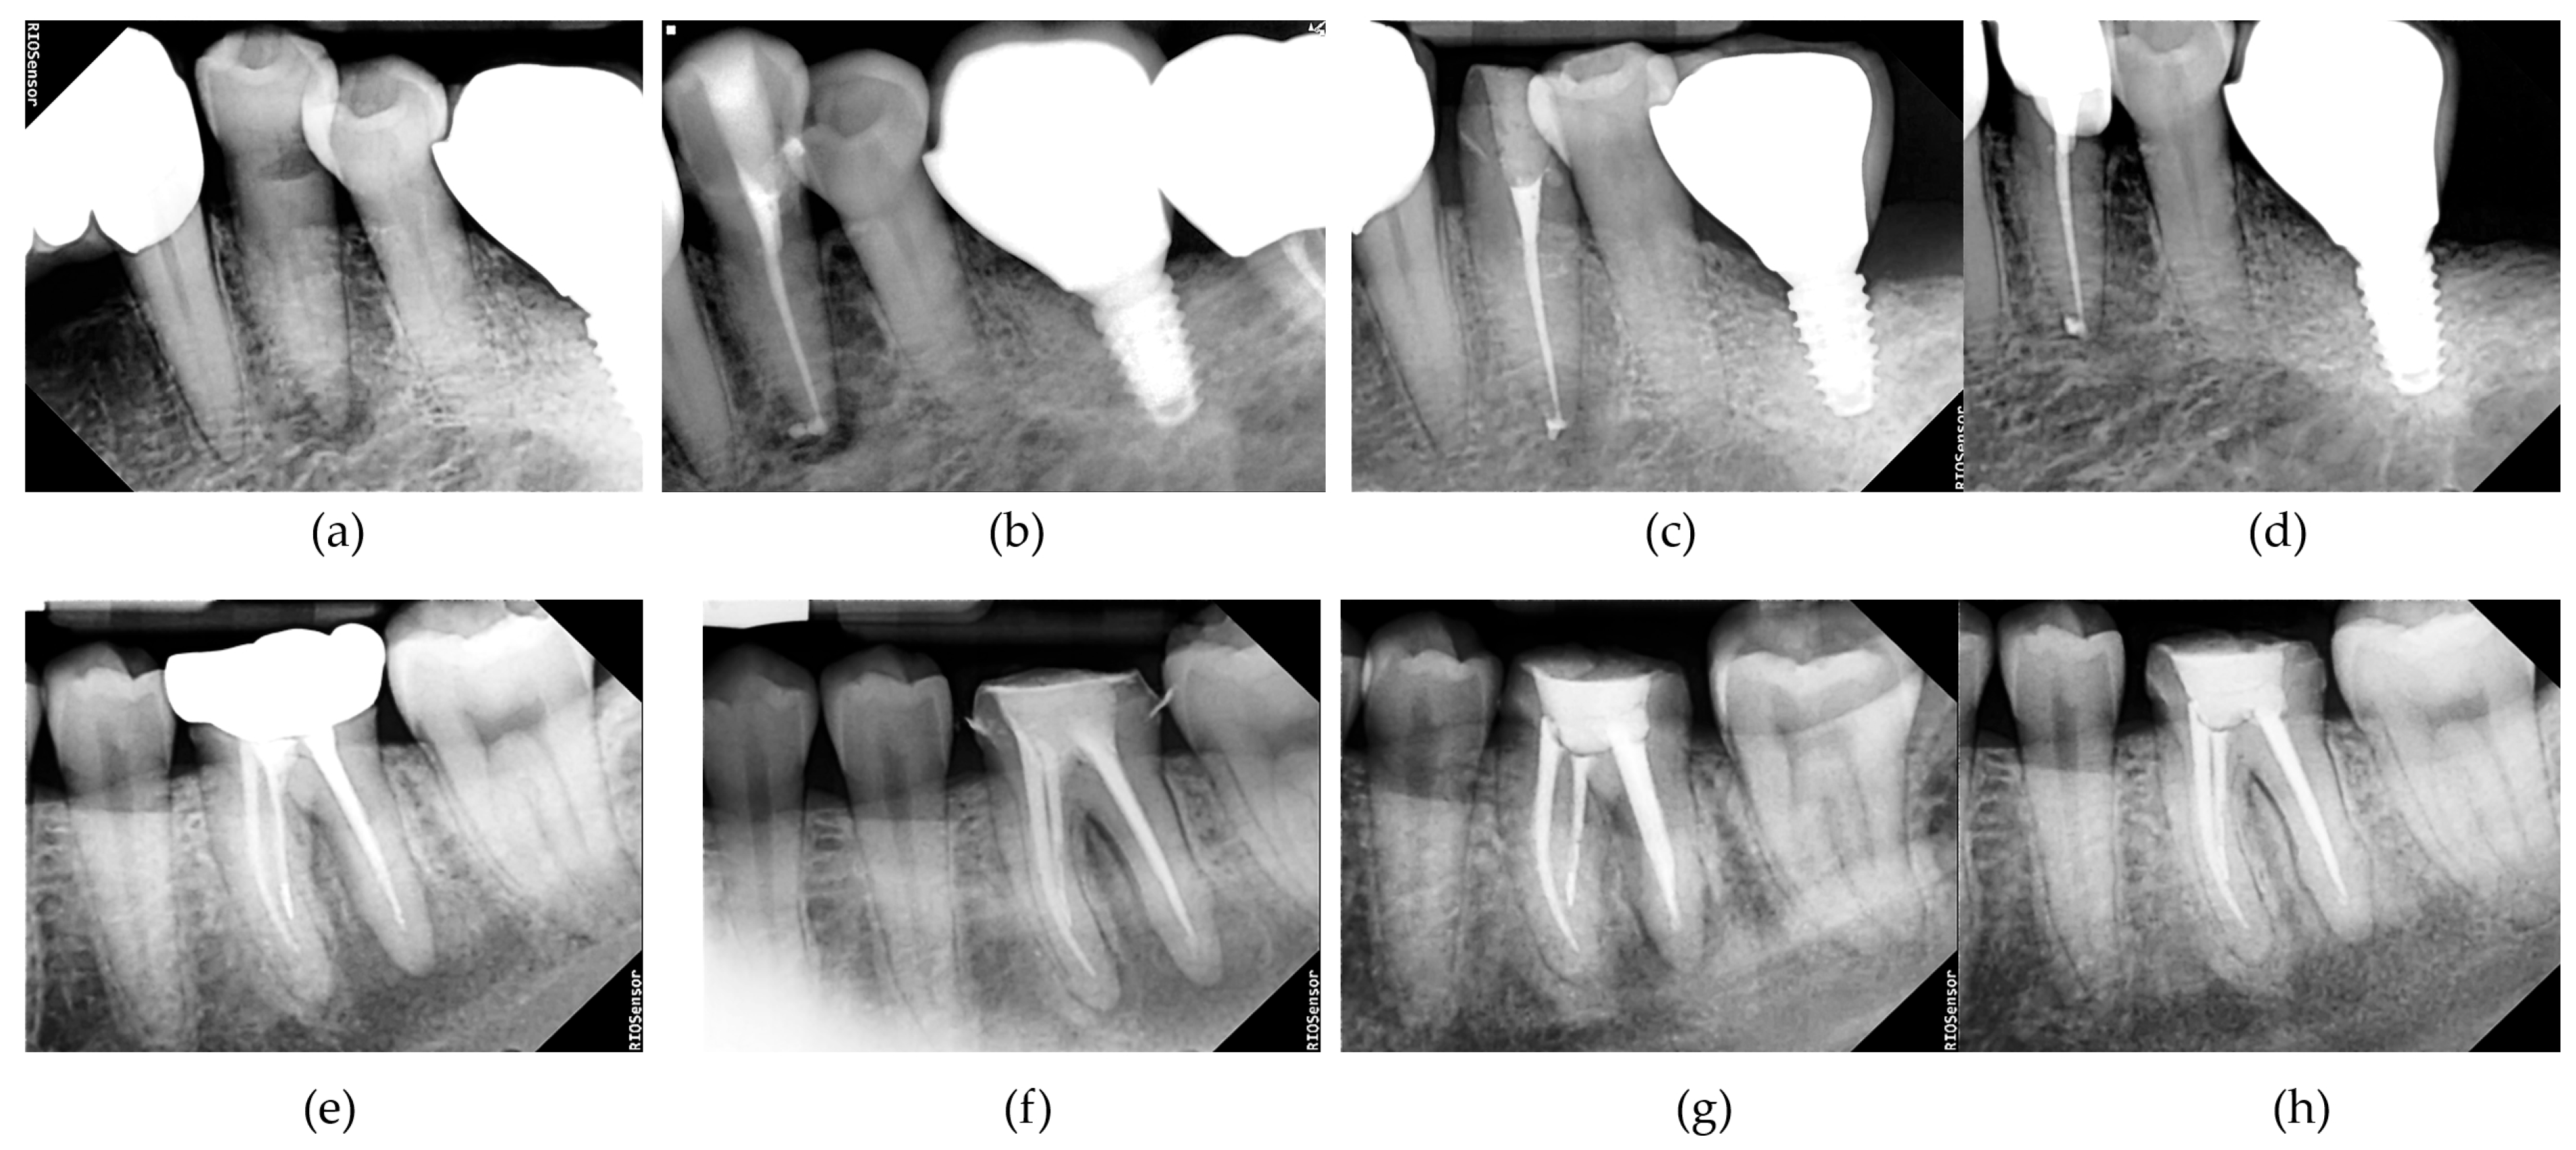

3.2. Radiographic Outcomes

| Time | Mean PAI Score Mean ± SD | p Value | |

|---|---|---|---|

| UDP | NaOCl | ||

| Preoperative | 2.46 ± 1.24 | 2.16 ± 1.08 | 0.603 |

| Canal Filling | 2.45 ± 1.24 | 1.98 ± 0.77 | 0.376 |

| 2 months | 1.96 ± 0.88 | 1.71 ± 0.71 | 0.511 |

| 4 months | 1.66 ± 0.79 | 1.43 ± 0.62 | 0.401 |